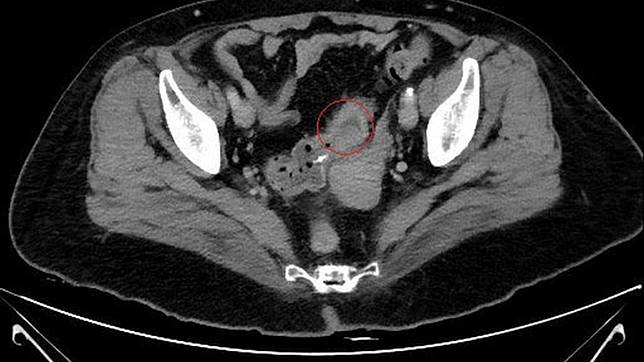

影像檢查發現秦媽媽直腸處的惡性腫瘤。圖/台北慈濟醫院提供

台北慈濟醫院指出,69歲的秦媽媽身體向來健康,也沒有癌症家族病史,但最近3、4個月以來卻偶爾出現血便症狀,期間前往衛生所進行大腸癌篩檢,證實糞便潛血檢查呈陽性反應,隨後轉往醫院作進一步電腦斷層掃描,在直腸處發現一顆5公分大小的惡性腫瘤,已經侵犯周圍器官,確診為直腸癌第三期。